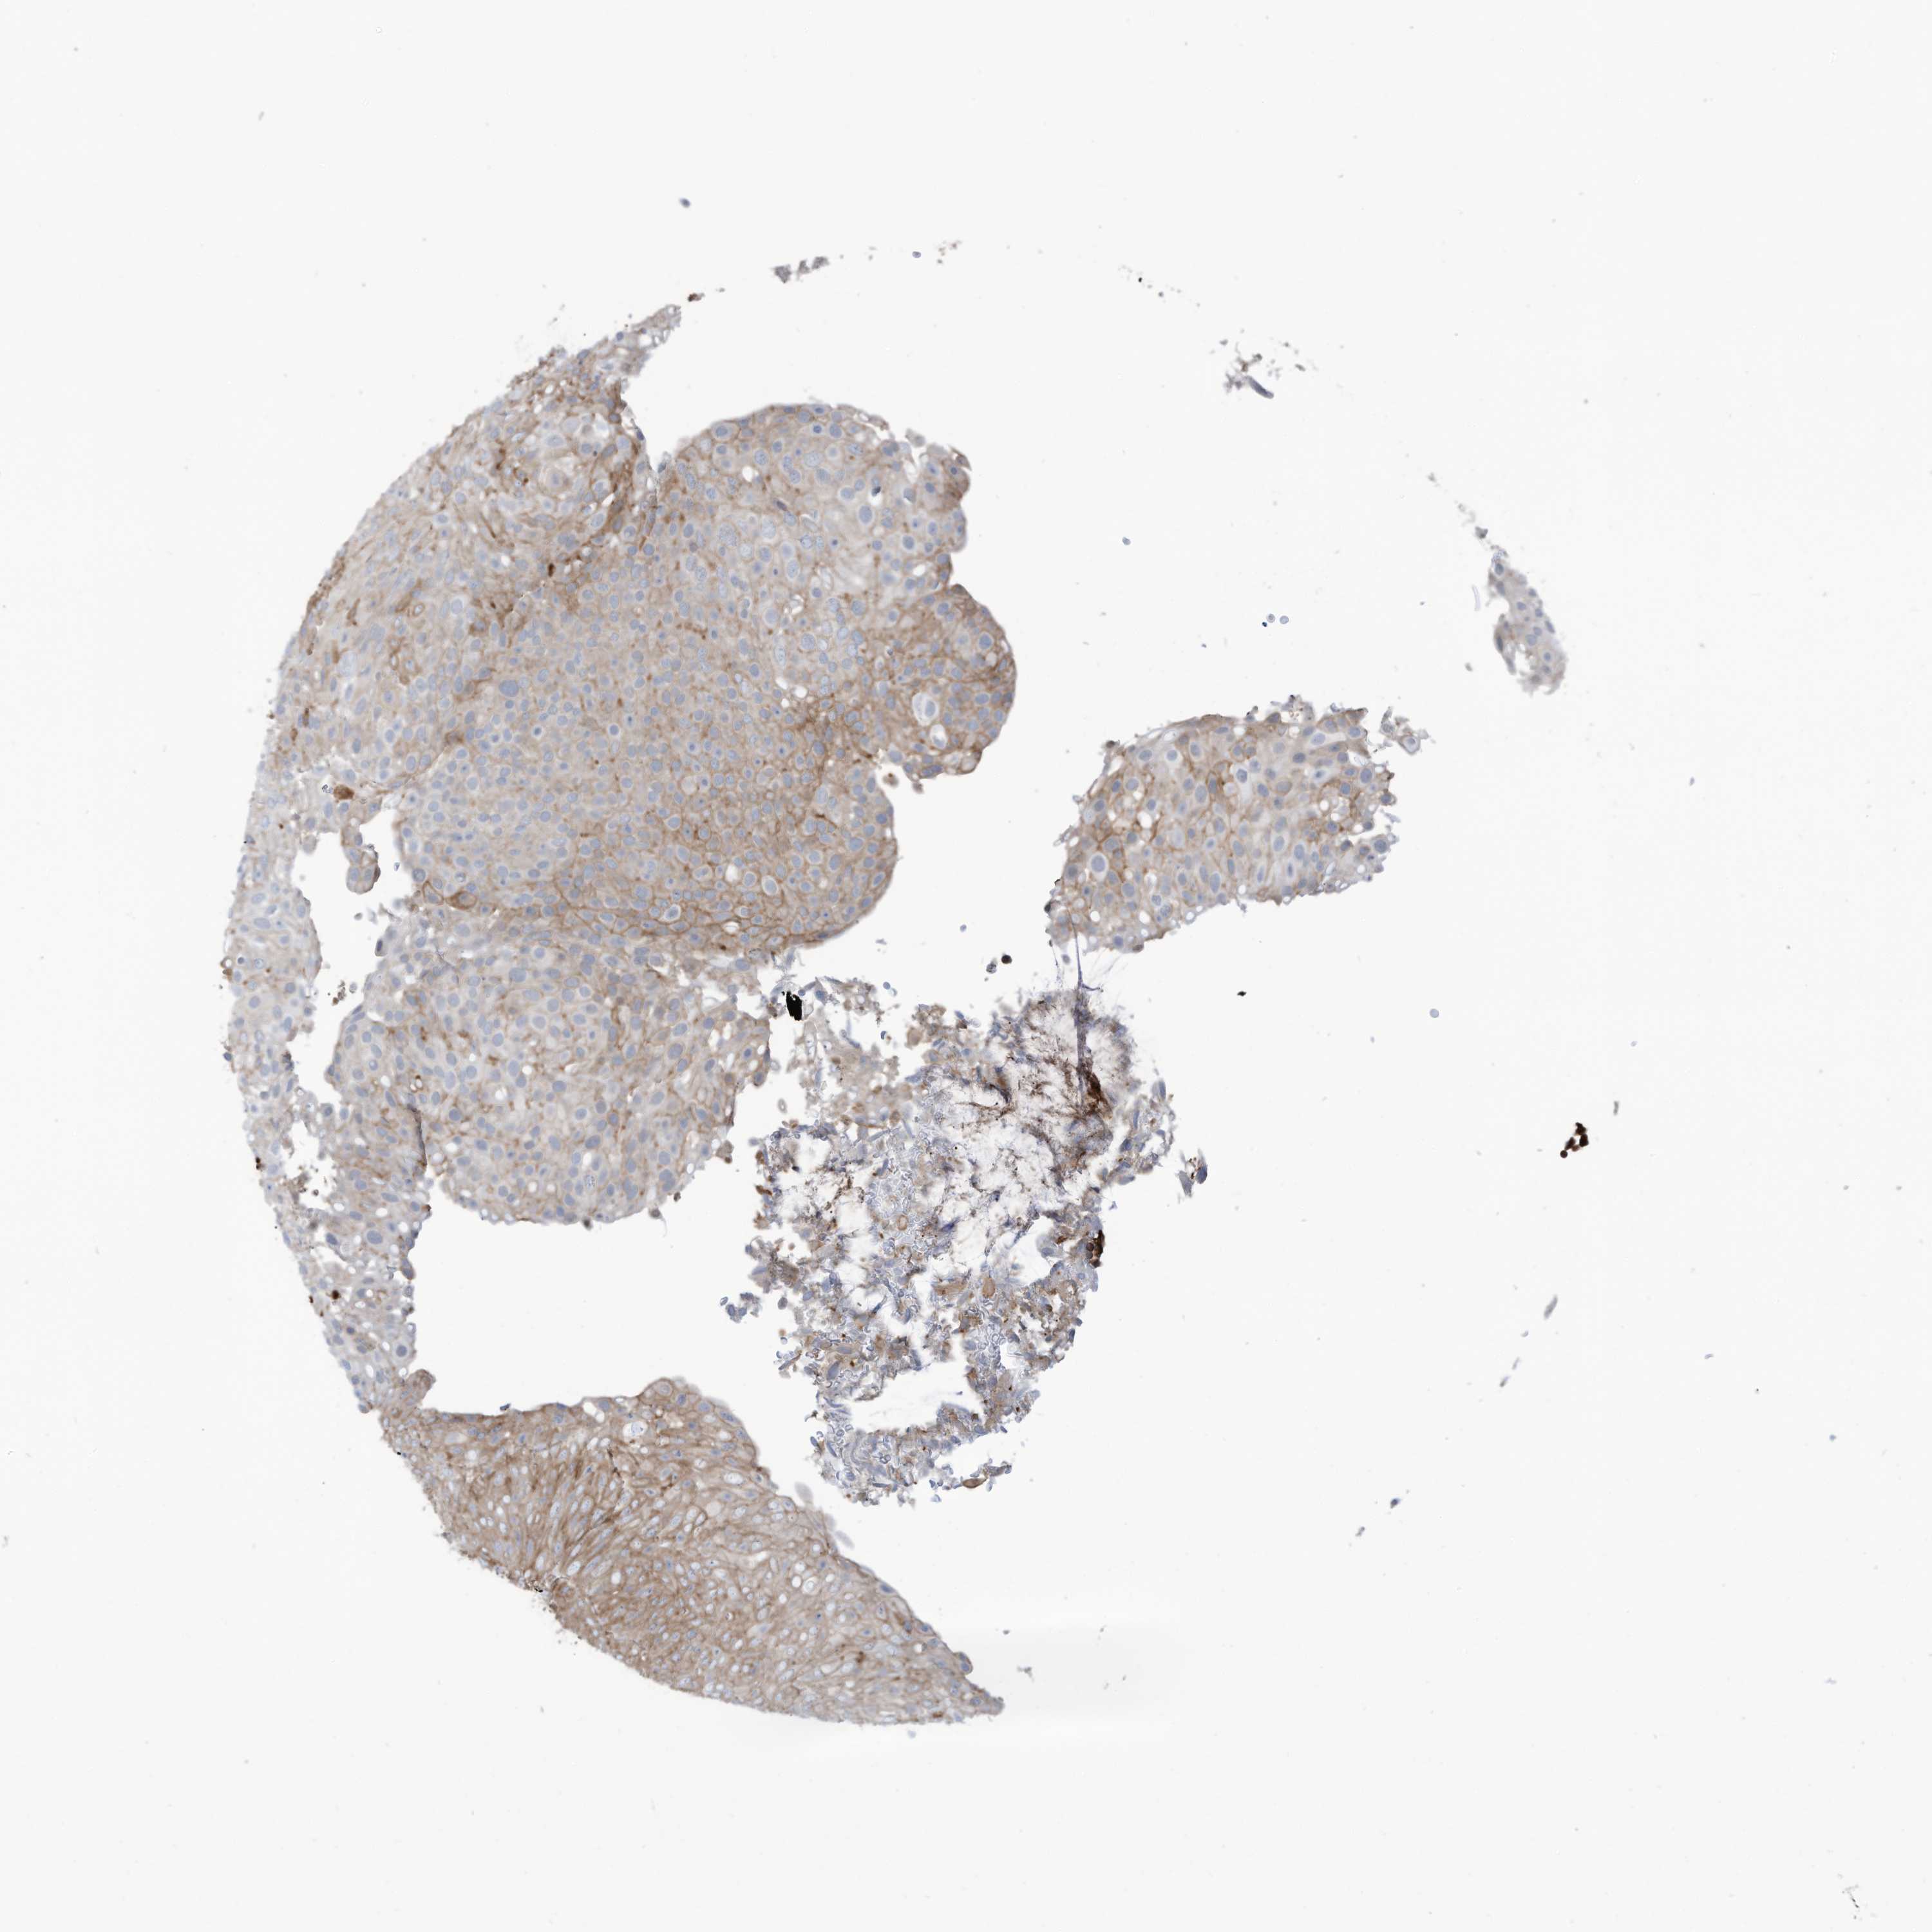

UROTHELIAL CANCER - Protein expressioni

A mouse-over function shows sample information and annotation data. Click on an image to view it in a full screen mode. Samples can be filtered based on level of antibody staining by selecting one or several of the following categories: high, medium, low and not detected. The assay and annotation is described here.

Note that samples used for immunohistochemistry by the Human Protein Atlas do not correspond to samples in the TCGA dataset.

Antibody stainingi

Antibody staining in the annotated cell types in the current human tissue is reported as not detected, low, medium, or high, based on conventional immunohistochemistry profiling in selected tissues. This score is based on the combination of the staining intensity and fraction of stained cells.

Each image is clickable and will lead to virtual microscopy that enables deeper exploration of all samples and also displays staining intensity scores, fraction scores and subcellular localization as well as patient and tissue information for each sample.

Antibody HPA035121

Antibody HPA035122

Staining

High

Medium

Low

Not detected

Intensity

Strong

Moderate

Weak

Negative

Quantity

>75%

75%-25%

<25%

None

Location

Nuclear

Cytoplasmic/membranous

Cytoplasmic/membranous,nuclear

Urothelial carcinoma, High grade

Urothelial carcinoma, Low grade